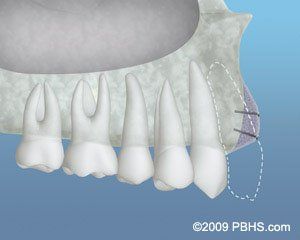

About Gum Grafting

To solve these problems, a gingival graft is designed.

A thin piece of tissue is removed from the mouth roof or moved gently from adjacent areas to provide a stable band of attached gingiva around the tooth.

The gingival graft may be put to cover the root's exposed part. The procedure of gingival grafting is highly predictable and results in a stable, healthy band of attached tissue around the tooth. Contact our office today to schedule an appointment!